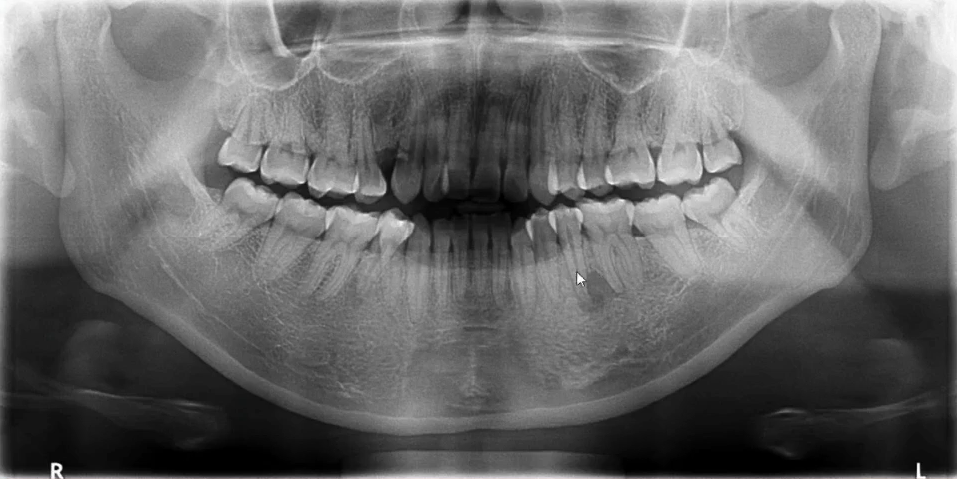

【病例3】

女,27岁,牙疼来院就诊

曲面断层片怎么看口腔精读 | 一次性教你看懂曲面断层片!_https://www.jmylbn.com_新闻资讯_第45张

18残根、38牙根方高密度影、36根尖炎、46根尖炎

48水平阻生

42根管内充填影,未到根尖

曲面断层片怎么看口腔精读 | 一次性教你看懂曲面断层片!_https://www.jmylbn.com_新闻资讯_第46张

其他问题:14、24、34、44牙缺失,为什么?

45根尖有阴影,是不是炎症?那35根尖呢?

36、46只是根尖炎?

42根尖有没有囊肿?

进一步检查:口腔CBCT的应用

36、46根管评估,45根尖颏孔鉴别诊断

42根尖区低密度影鉴别诊断

38根尖区高密度影鉴别诊断

进一步检查:临床病史询问——正畸

临床检查——关节、面型等(曲断片读片)